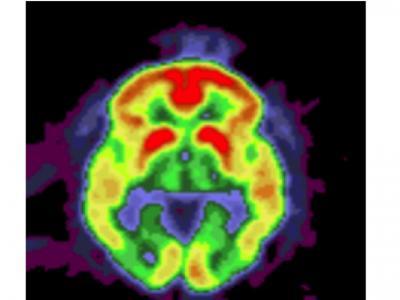

The PET image of the brain shows a build up of amyloid deposits (highest amounts in yellow and red) in a patient with Alzheimer's disease.

(Photo Credit: Knight Alzheimer's Disease Research Center)